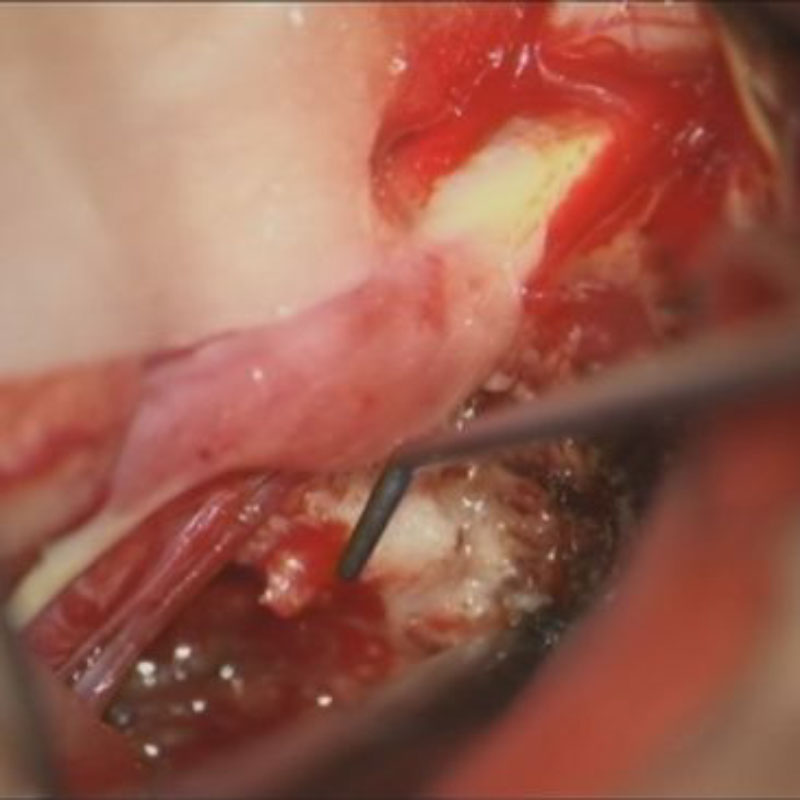

412

'23年5月

20代

小脳血管芽腫

頭蓋内腫瘍摘出術

No.’23_46 手術前1

No.’23_46 手術前2

No.’23_46 摘出 前

No.’23_46  摘出 中

No.’23_46 摘出 後